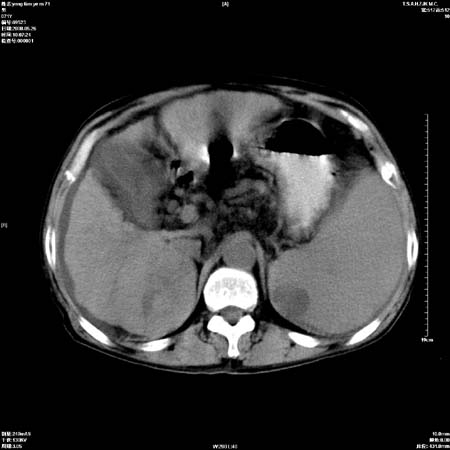

以下是引用医影拾贝在2008-6-5 22:48:00的发言:[br]肝硬化、门脉高压、胃底食管静脉曲张、低蛋白血症(胆囊壁水肿、增厚)、腹水[br]脾功能亢进、脾大、脾、左肾囊肿[br]肝囊性占位、不除外肝脓肿可能[br]建议增强以除外肝右叶肝ca可能

以下是引用chenglinhunan在2008-6-5 22:53:00的发言:[br]1. 肝硬化腹水,脾肿大。[br]2. 肝右后叶占位,肝癌。[br]3。建议ct增强扫描。

以下是引用xulianj在2008-6-5 21:40:00的发言:[br]支持肝硬化腹水;建议增强。肝、脾、肾囊肿待排。

以下是引用zjzjr在2008-6-6 12:34:00的发言:[br]1. 肝硬化腹水,脾肿大。[br]2. 肝右后叶占位,肝癌。[br]3。建议ct增强扫描。[br]4肝脾囊肿.